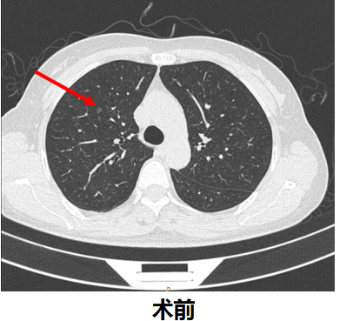

近日,我院成功利用O型臂CT联合真易达®穿刺机器人内镜介入诊疗平台,为一名51岁女性患者实施5毫米纯磨玻璃肺结节氩氦刀消融术。该技术以“快速、精准、安全”为核心理念,突破传统CT引导局限,标志着肺结节微创治疗迈入智能三维精准时代。

患者女性,51岁,随访中发现肺部纯磨玻璃结节逐渐增大,经评估需行消融治疗。传统CT引导穿刺面临定位耗时长、辐射量高、操作复杂等挑战,而本次手术采用O型臂CT+真易达®穿刺机器人组合方案,优势显著: